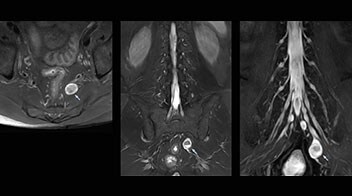

At Northern Fukushima Medical Center in Japan, excellent MRI visualization of nerves helps support confident diagnoses and informs surgical treatment decisions for patients with lower limb symptoms. MRI technologist Tanji and orthopedic surgeon Dr. Yabuki share how direct nerve visualization with the 3D NerveVIEW method adds information when diagnosing atypical herniations. The additional insights changed their way of working and benefit their patient care, as illustrated by some clinical examples.

“In patients with lower extremity neurological symptoms, NerveVIEW helps us to determine the disease matching the patient’s symptoms by directly visualizing the nerves. We use the sequence mainly, when there is suspicion of intraforaminal stenosis, extraforaminal stenosis or lateral disc herniation, which is often based on routine T2- and T1-weighted images. Additionally, the excellent depiction of the course of nerves makes NerveVIEW a good navigator when applying treatment such as block therapy or surgery.”

Northern Fukushima Medical Center (NFMC) Imaging Center uses the 3D NerveVIEW sequence for performing MR neurography, particularly in patients with pain and weakness in the lower limb. “It is included in about 20% of the approximately 150 lumbar spine MRI exams each month at NFMC, and can help us to determine if structures are impinging on the nerves,” says Hajime Tanji, RT, MRI technologist at NFMC.

“In such case, we would then browse through axial T2-weighted MR images slice by slice and mentally reconstruct the actual situation based on both radiculography and MRI. Fortunately, NerveVIEW can now very well show nerve courses and presence of nerve compression or edema in one single image series.” “We have often seen NerveVIEW directly depict details of the nerve compression that were not observed by radiculography. Therefore, we think that with NerveVIEW we can reduce the number of invasive examinations, especially for some patients with lumbar plexus symptoms.”

“Before NerveVIEW, diagnosis by MRI alone was sometimes difficult, unless there was a strong suspicion based on clinical symptoms,” says Shoji Yabuki, MD, DMSc, Orthopedic surgeon at Fukushima Medical University School of Medicine. “This is why we routinely perform selective lumbosacral radiculography (nerve root block) and x-ray in such cases. However, radiculography can only depict nerves as far as the contrast agent reaches. When a nerve is distorted by compression, the contrast agent will not pass through this compressed area, preventing us from evaluating the full nerve compression.”

The key concept in MR neurography, Dr. Yabuki stresses, is the ability to directly visualize spinal nerves, versus inferring the presence of pathology indirectly. “Before NerveVIEW, we estimated compression of the nerve by looking for the presence or absence of fat signal on other MR images,” he says.

“For example, in sagittal images, when the presence of fat is observed in the intervertebral foramen, it suggests that there is a margin around the nerve. Similarly, the absence of fat indicates that the nerve is being compressed. So, we used to deduce nerve compression indirectly. With NerveVIEW, however, we can observe the condition of the nerves directly, regardless of the presence or absence of fat. We always prefer such direct observation of anatomy over having to make an inference about it.”

“Although symptoms of typical disc herniation and atypical hernia are very similar, the actual site of herniation is different. It is therefore important to characterize the nerve’s condition both inside and outside of the intervertebral foramina. “Conversely, if we see no abnormality in NerveVIEW, we can assume at least that there is no severe condition that requires surgery. Like this, it can help us avoid unnecessary surgery. NerveVIEW can have a tremendous impact in this way.”

“NerveVIEW is really useful for those cases where a nerve disorder is strongly suspected based on the clinical examination but our regular MRI images do not show any findings. These atypical herniations and spinal canal stenosis, occurring in 5% to 15% of the total lumbar herniation/stenosis cases are our main target when using NerveVIEW,” says Dr. Yabuki.